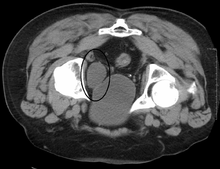

Urinary bladder (black butterfly-like shape) and hyperplastic prostate (BPH) visualized by Medical ultrasonography technique.